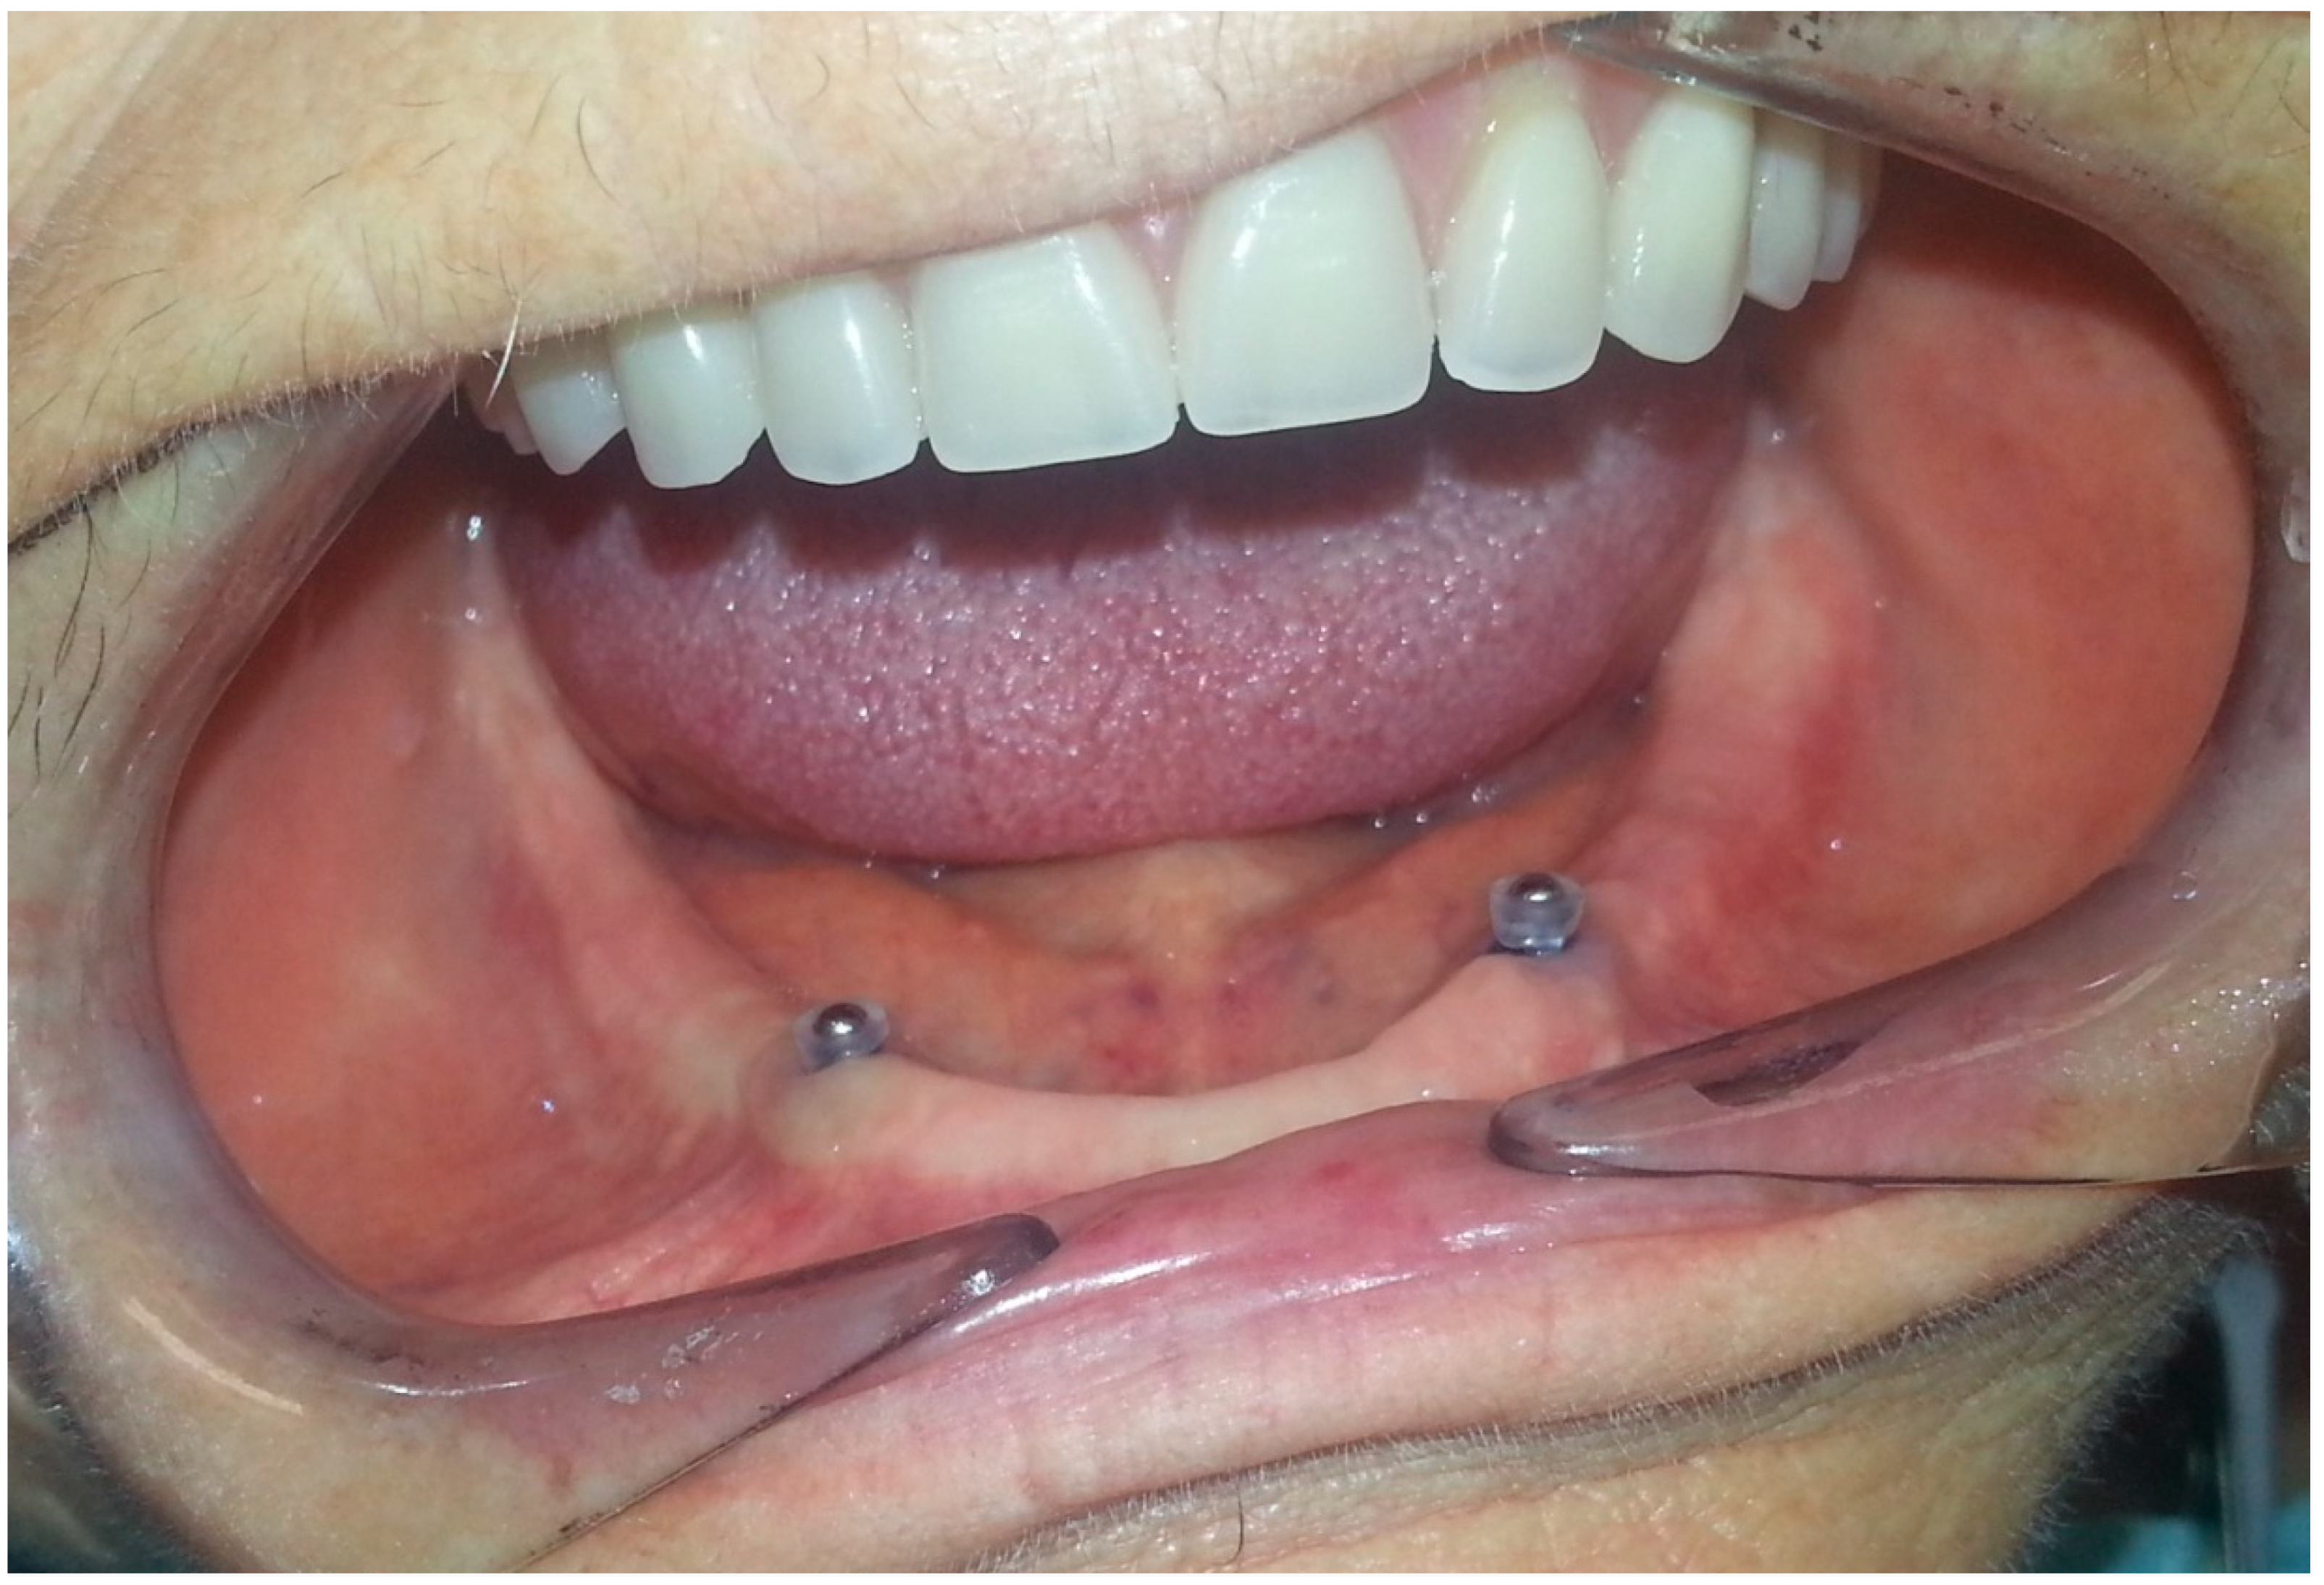

- After 7 days, the Teflon/o-ring is replaced. After preparing the housing for the Teflon on the mobile prosthesis and evaluating the necessary height, insert the small silicone tube cut at the right height in the ball-attachment. Then, the Teflon is inserted. The silicone tube adheres superiorly to the Teflon inferiorly to the gingiva protecting the entire retentive attachment (Figure 4, Figure 5, Figure 6 and Figure 7). After mixing the acrylic resin and inserting it in the right quantity (filling the previously prepared cavity 50%), the prosthesis is fitted into the oral cavity, causing the patient to close in full intercuspidation and waiting for polymerization (Figure 8, Figure 9 and Figure 10). Once the polymerization has taken place, the mobile prosthesis can be removed very easily as the acrylic resin will be present only around the Teflon and will have filled all the walls of the cavity previously prepared leaving them smooth; there may be small smears of resin that will easily be removed in a short time with the aid of rubber pads (Figure 11).